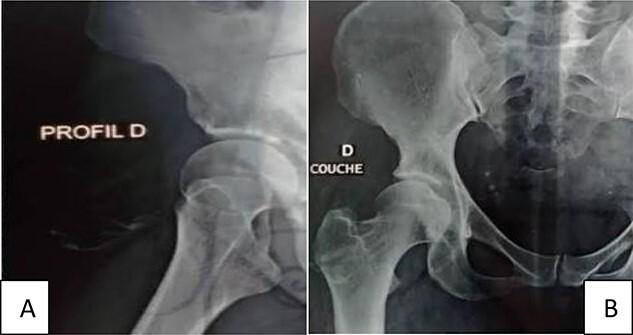

骨脂肪瘤是一种非常罕见的良性肿瘤,预后良好。它主要由成熟脂肪组织和骨成分组成。鉴于其临床和放射学特征可能模拟其他良性或恶性病变,诊断基于组织学研究。骨肉瘤是主要的鉴别诊断对象。区分这两种肿瘤至关重要,因为治疗基础不同。我们报告一例位于大腿的、与骨组织无关的巨大骨化性脂肪瘤患者的病例。